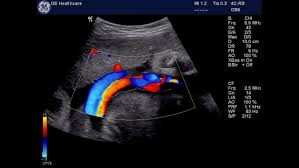

La adquisición de un ecocardiógrafo de última generación, una sonda para estudios cardiológicos a través del esófago y programas informáticos únicos en la región permitirán que el efector público ubicado en Avenida Freyre y Salta concrete exámenes inéditos en la provincia. Asimismo, el hospital Cullen incorporó software para realizar resonancias magnéticas del corazón.